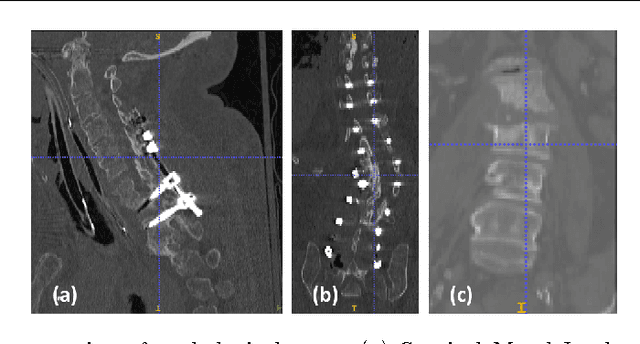

Abstract:Automatic localization and labeling of vertebra in 3D medical images plays an important role in many clinical tasks, including pathological diagnosis, surgical planning and postoperative assessment. However, the unusual conditions of pathological cases, such as the abnormal spine curvature, bright visual imaging artifacts caused by metal implants, and the limited field of view, increase the difficulties of accurate localization. In this paper, we propose an automatic and fast algorithm to localize and label the vertebra centroids in 3D CT volumes. First, we deploy a deep image-to-image network (DI2IN) to initialize vertebra locations, employing the convolutional encoder-decoder architecture together with multi-level feature concatenation and deep supervision. Next, the centroid probability maps from DI2IN are iteratively evolved with the message passing schemes based on the mutual relation of vertebra centroids. Finally, the localization results are refined with sparsity regularization. The proposed method is evaluated on a public dataset of 302 spine CT volumes with various pathologies. Our method outperforms other state-of-the-art methods in terms of localization accuracy. The run time is around 3 seconds on average per case. To further boost the performance, we retrain the DI2IN on additional 1000+ 3D CT volumes from different patients. To the best of our knowledge, this is the first time more than 1000 3D CT volumes with expert annotation are adopted in experiments for the anatomic landmark detection tasks. Our experimental results show that training with such a large dataset significantly improves the performance and the overall identification rate, for the first time by our knowledge, reaches 90 %.